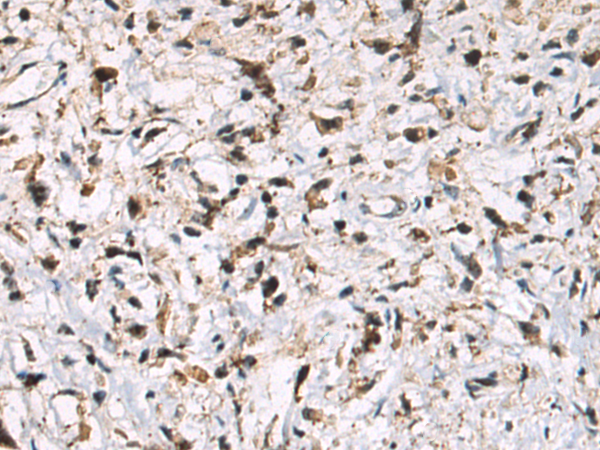

分类: 科研抗体货号: P10612别名: AMY-1应用: IHC反应种属: Human, Mouse